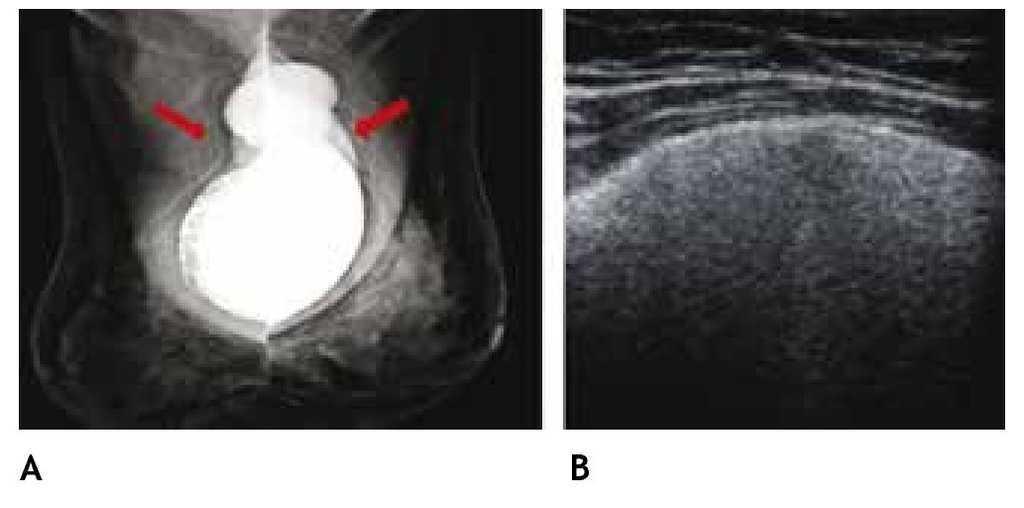

El ultrasonido es utilizado en la mayoría de las mastografías diagnósticas, sobre todo en el estudio de patología benigna y permite la evaluación inicial de la paciente con implantes mamarios y complicaciones, como la ruptura extracapsular (figs. 8A y B). El estudio de la región retroareolar, proporciona información detallada de los conductos galactóforos.

Figura 8 A) Mamaplastía de aumento hace 15 años. Radiografía de mínima compresión, prótesis de silicón, subpectorales, con calcificación de la cápsula fibrosa derecha y silicón libre bilateral (flechas). B) Ultrasonido con signo de la "tormenta de nieve", BIRADS 2: ruptura extracapsular.